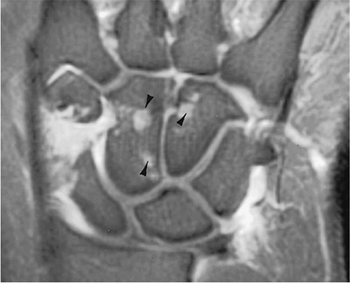

FIGURE 13-2 Coronal contrast-enhanced fat-suppressed T1-weighted image demonstrates early changes of RA with erosions (arrowheads) and synovial enhancement.